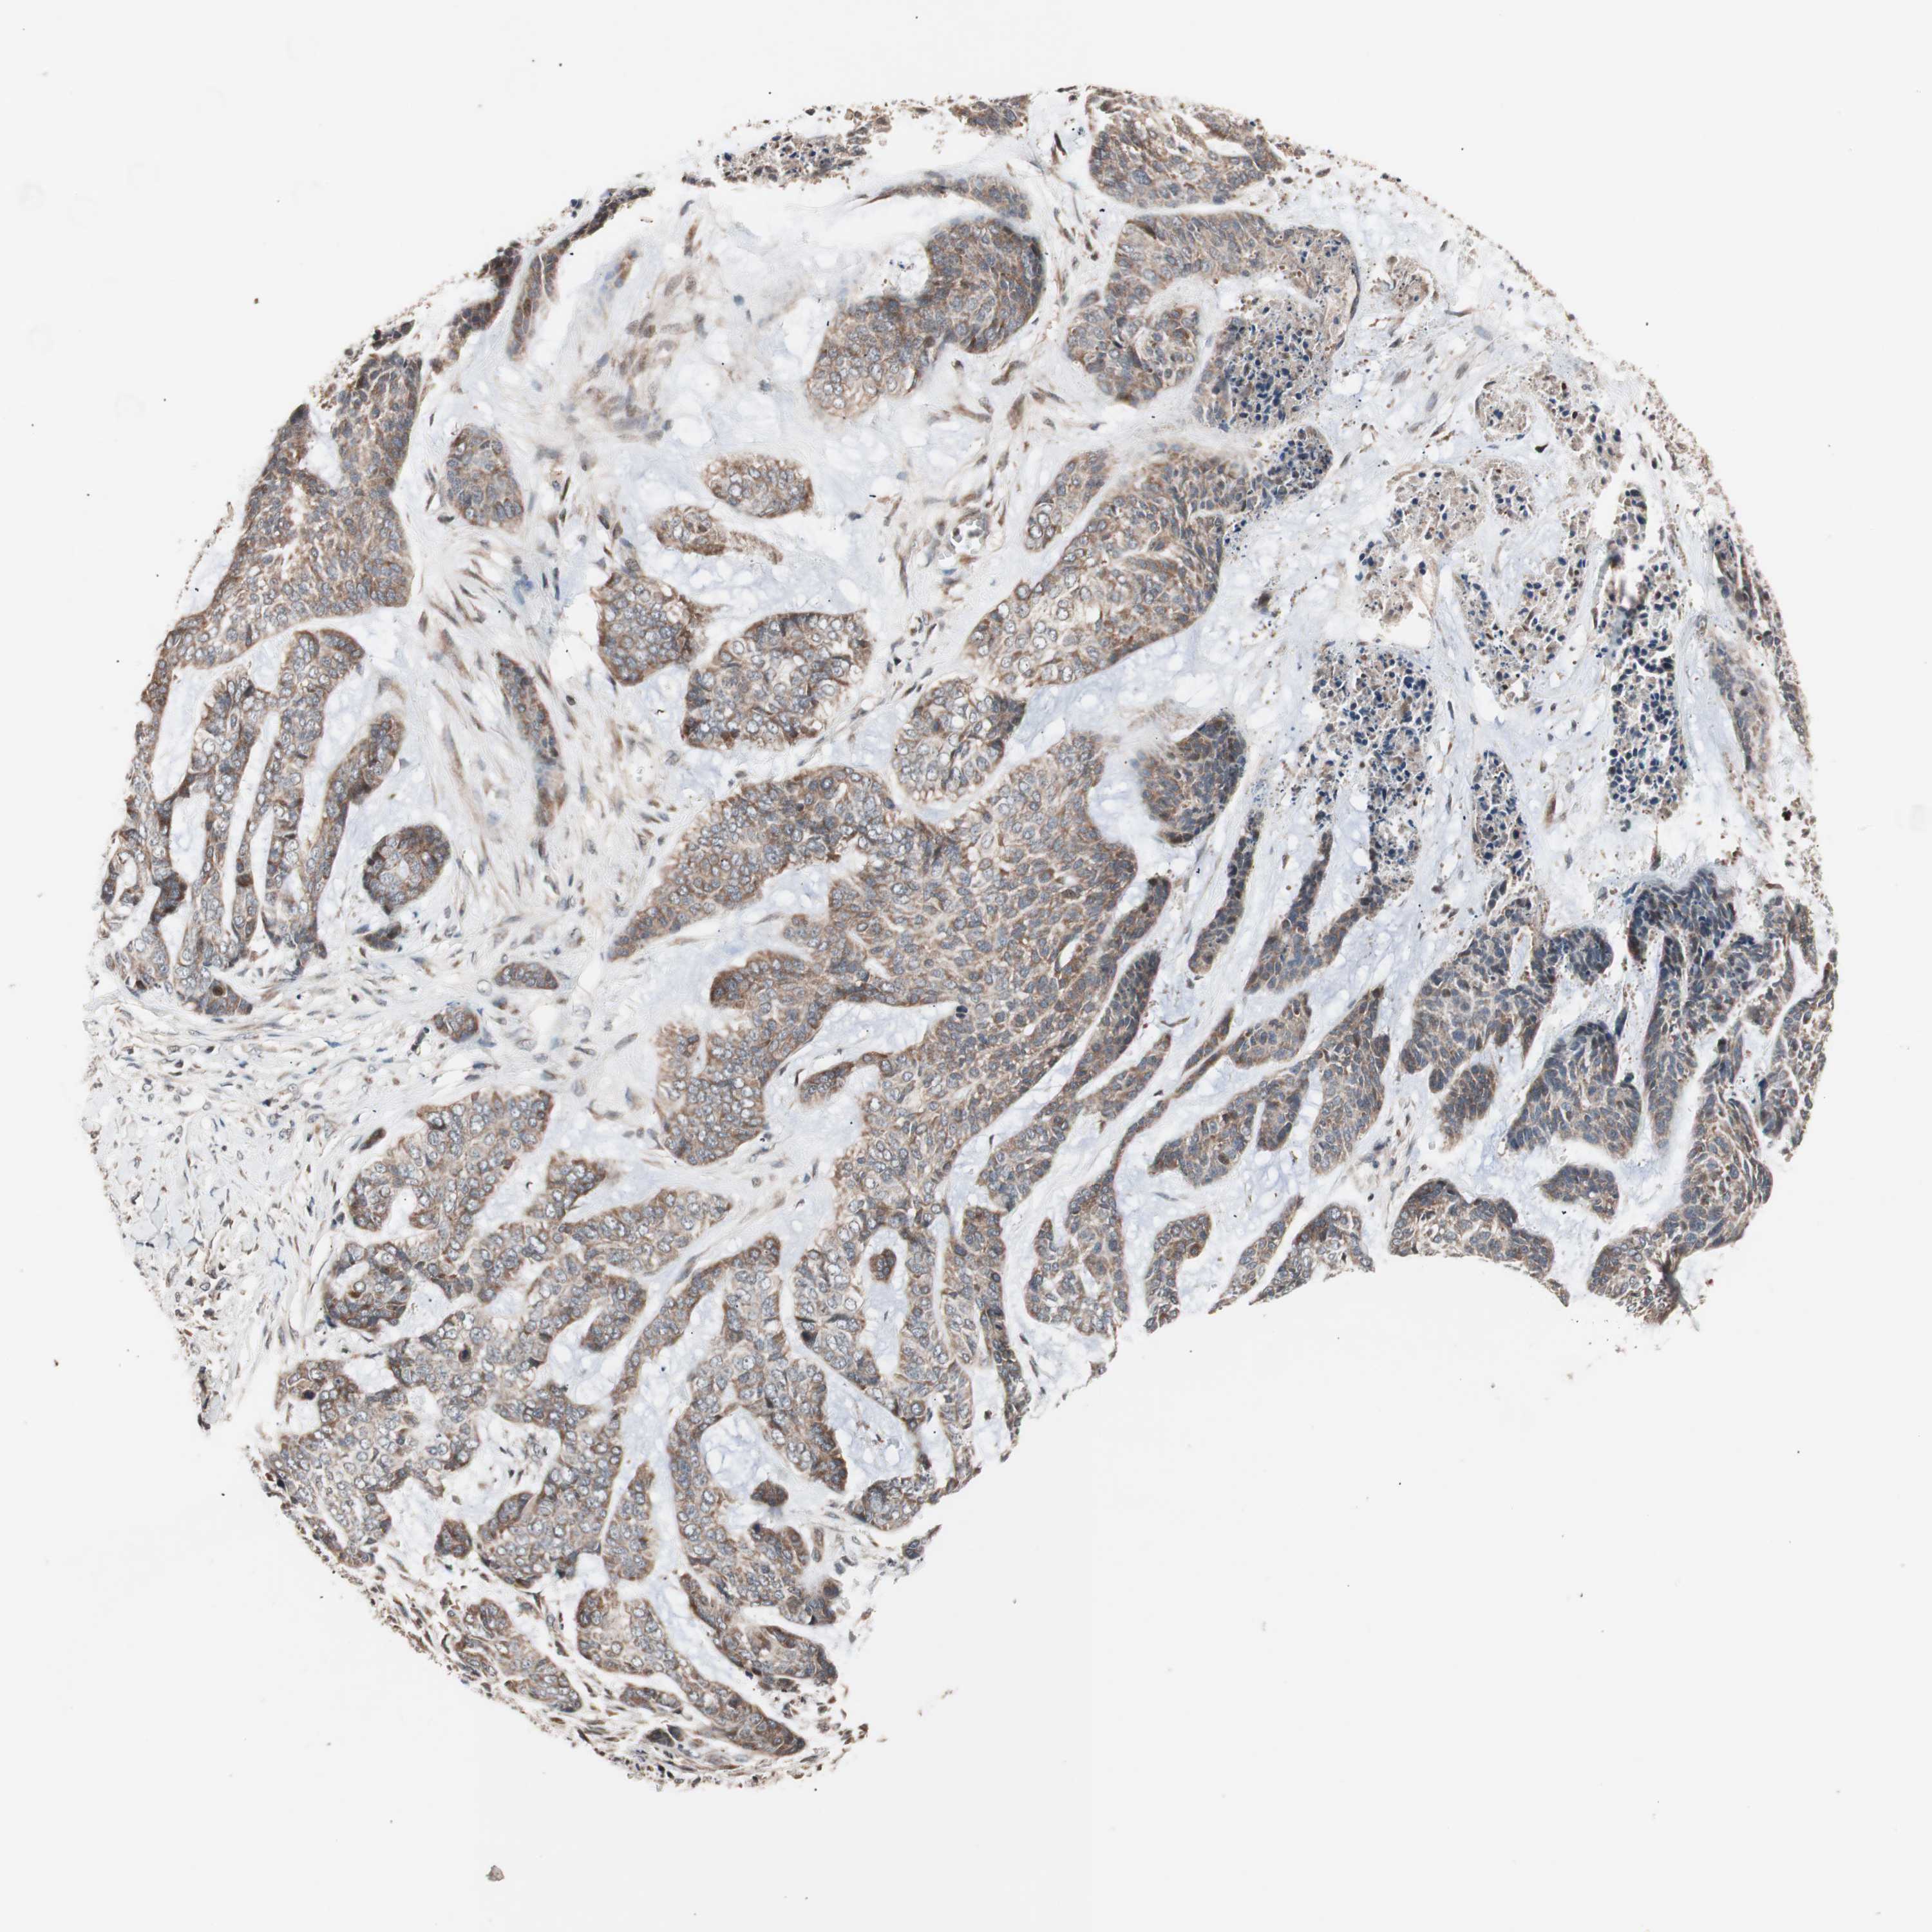

SKIN CANCER - Protein expressioni

A mouse-over function shows sample information and annotation data. Click on an image to view it in a full screen mode. Samples can be filtered based on level of antibody staining by selecting one or several of the following categories: high, medium, low and not detected. The assay and annotation is described here.

Each image is clickable and will lead to virtual microscopy that enables deeper exploration of all samples and also displays staining intensity scores, fraction scores and subcellular localization as well as patient and tissue information for each sample.

Antibody HPA003097

Squamous cell carcinoma, NOS